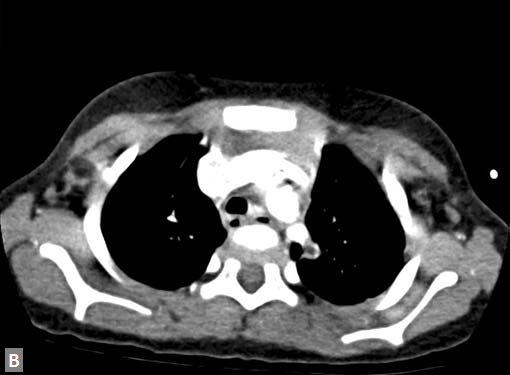

Largest possible intravenous cannula should be used. Patency of intravenous access can be confrmed by injecting saline at high pressure. Newer power (pressure) injectors have software which prevents contrast extravasation into soft tissues. Whenever contrast (5–10 mL) escapes inadvertently into soft tissues, the increase in pressure is sensed by the pressure injector and it stops further pumping of contrast. Rate of contrast injection is 5–6 mL/second. Rate can be reduced in patients with smaller built and children. Saline chase is used for coronary evaluation. Saline chase is not given in study for “triple” rule out (Figs 1A to C).

Filling defects (Figs 16A and B) may be seen in main

pulmonary artery (MPA), left pulmonary artery (LPA) and

right pulmonary artery (RPA), interlobar artery, segmental

divisions (Figs 17A and B). On occasions, detection in distal

parts of segmental divisions is difficult. This can be further

confounded by motion artifacts, non- or minimally opacified

accompanying pulmonary veins.